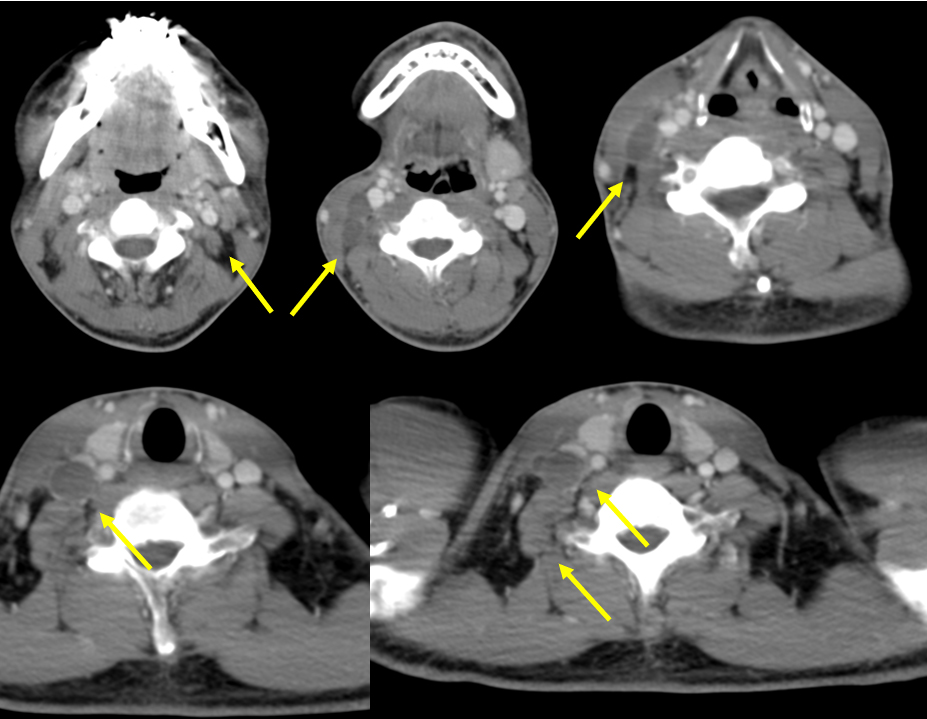

【画像所見まとめ】

• 右頸部に多発する嚢胞性(または壊死性)病変、リンパ節腫大

【その後の経過】

右頸部リンパ節、膿瘍、脾結節は縮小(抗菌薬なし)

新たに左頸部にリンパ節腫大出現膿瘍壊死のみ

【無菌性膿瘍の画像報告】

• 肝、脾